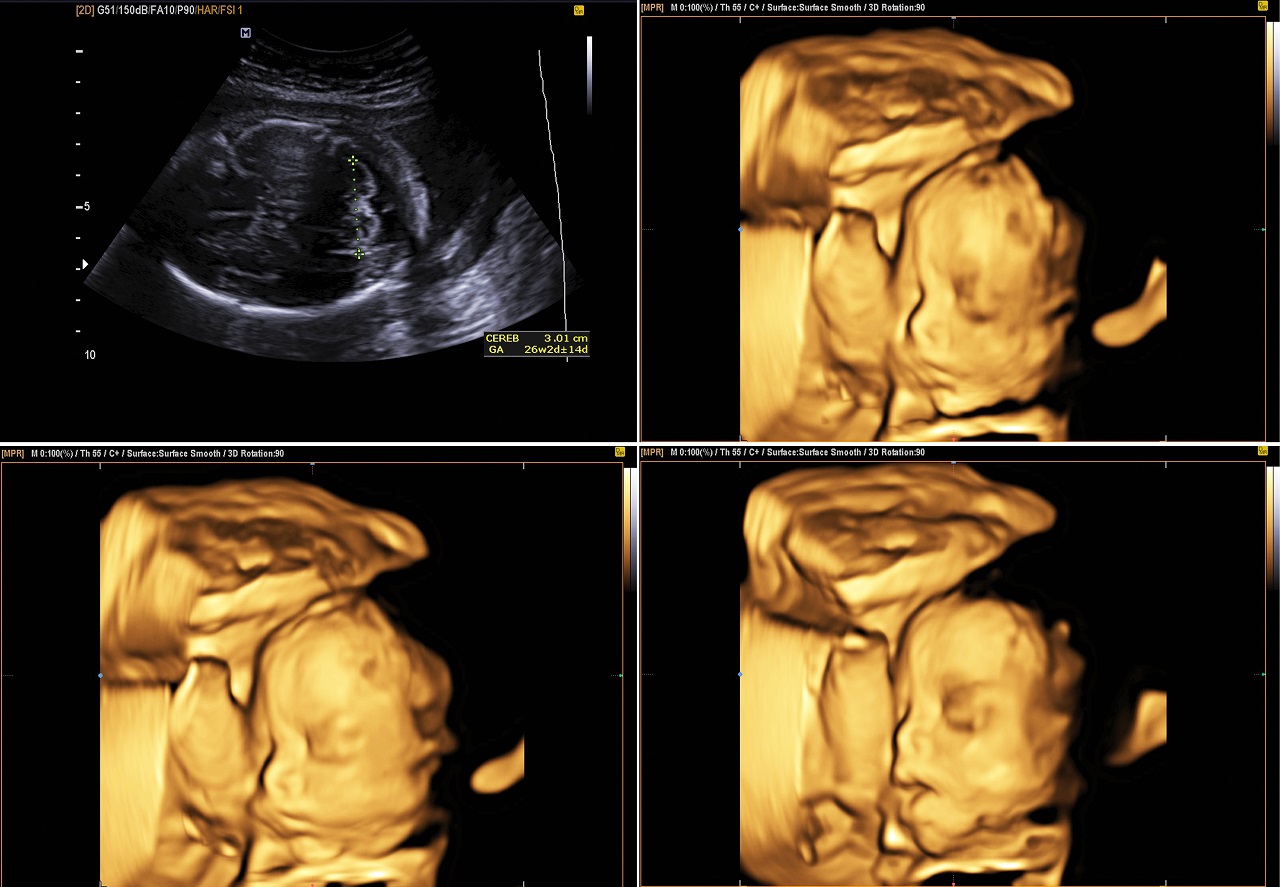

What are the benefits of a 4D Ultrasound?

- Much Clearer Picture Of The Baby’s Face

Much Clearer Picture Of The Baby’s Face

Although 2D and 3D scans can also examine the fetus, 4D ultrasound allows you to see your little one in the best way possible. It can give you a real-time 3-dimensional moving photo, allowing you to see your baby’s tiniest movements. Through the notable advantage that this ultrasound provides, doctors can hold a more comprehensive assessment of the fetal well-being. This can lead you to a healthier and happier pregnancy.